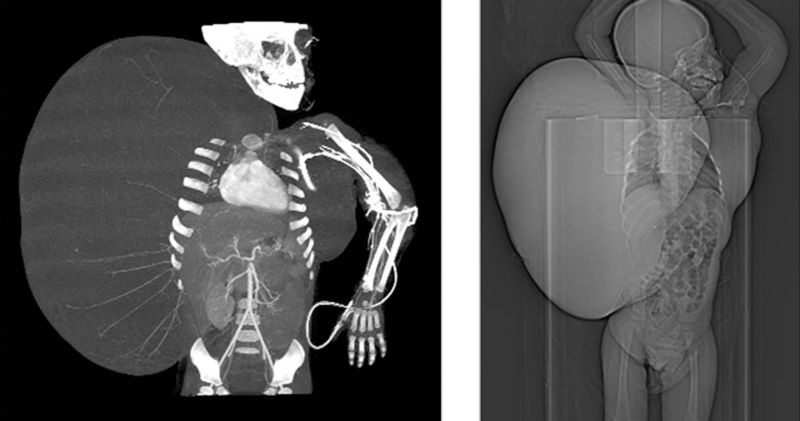

O tumor pesava mais do que o paciente, segundo o médico. "O menino chegou ao hospital pesando 27 quilos, dos quais mais da metade correspondia a uma má-formação grave, muito complexa, correspondente a um tumor que tinha se espalhado para parte do tórax e do abdômen", disse.

O menino, identificado pelo centro médico como Jesús Gabriel e originário do estado de Durango (norte), foi submetido a uma cirurgia de dez horas em 14 de junho e agora se recupera satisfatoriamente no hospital La Raza, do Instituto Mexicano de Previdência Social.